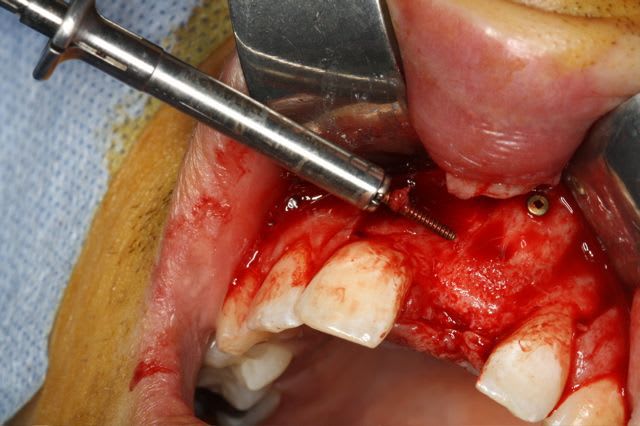

Pour le fun ! car pas bcp de photos en ce moment sur nonol

la dent était absente depuis 8 ans suite à "accident" de la vie (à 5h du mat'...)

très classiquement:

greffe onaly,

dépose des vis et pose de l'implant à 5mois1/2 avec un cj roulé et mise en place de la vis de cica,

et 3 mois 1/2 après empreinte

15j après essayage pilier et biscuit, visite au labo pour "finition en bouche" et 3 h après scellement.

pour la greffe: un lit de copeaux généreux et un bloc corticale par dessus et des copeaux pour boucher les espaces. Pas de membrane par dessus, seulement le périoste.